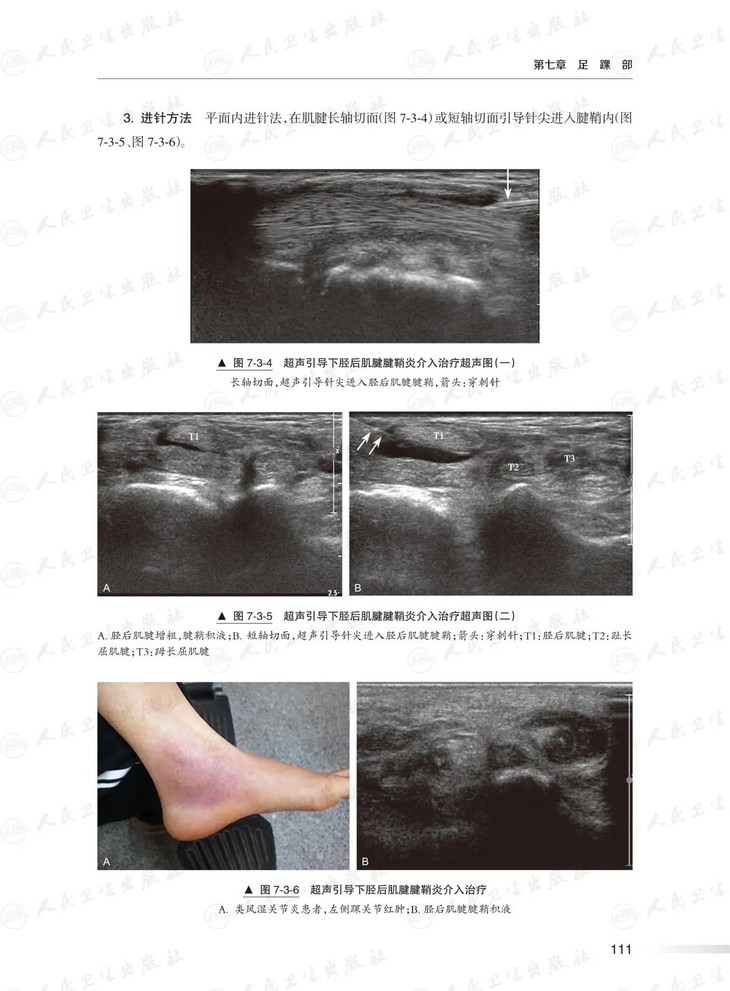

本书将全面涵盖人体肩关节、肘关节、手腕部、骨盆、膝关节及足踝部等6个部位的超声引导下介入操作,包括液体抽吸、药物注射、肌腱腱鞘穿刺、神经卡压松解、神经阻滞等等。各项操作均从相关解剖知识、适应症、要点和操作步骤进行全面地介绍,并插入了大量的解剖示意图、实物图和超声图像便于读者理解并遵照进行实践,对于初学者和有一定经验的操作者都非常实用, 广泛适用于超声科及相关临床科室如骨科、疼痛科、麻醉科、康复科等的医生。